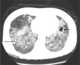

Multiple lung abscesses